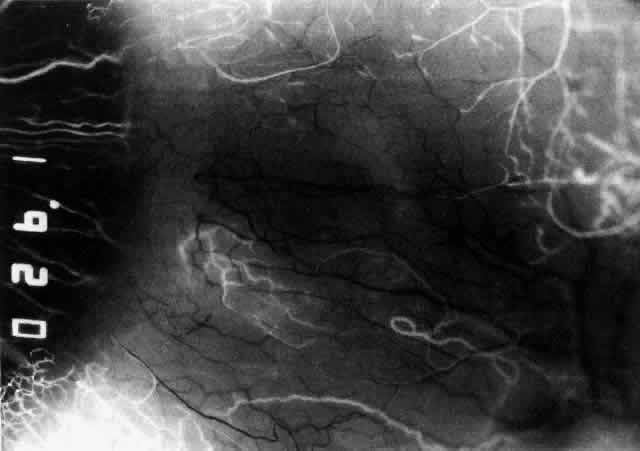

The characteristic features of necrotizing scleritis on fluorescein angiography are hypoperfusion and, eventually, nonperfusion of the vascular networks (Figs. 40 through 43).26 The initial changes are on the venous side of the capillary network; the transit time of the dye increases even if the eye is red and congested. If the disease process persists or has been present for a long time, thrombosis and permanent vaso-occlusive changes occur. These vessels (or the occluded capillary network) are bypassed by the opening of anastomotic channels. New vessels in a granuloma give rise to deep intrascleral leakage of dye (see Fig. 43). Conjunctival and episcleral involvement by the destructive change is late but is always preceded by vaso-occlusive changes that can sometimes be detected with use of the red-free light on the slit lamp (Figs. 44 and 45).

Fig. 43. Late venous phase of angiogram of a patient with necrotizing scleritis showing late deep leakage from vessels on the surface of the sclera and leakage of the capillary network at the limbus and the vessels draining it, together with poor or absent perfusion of the remaining vessels.